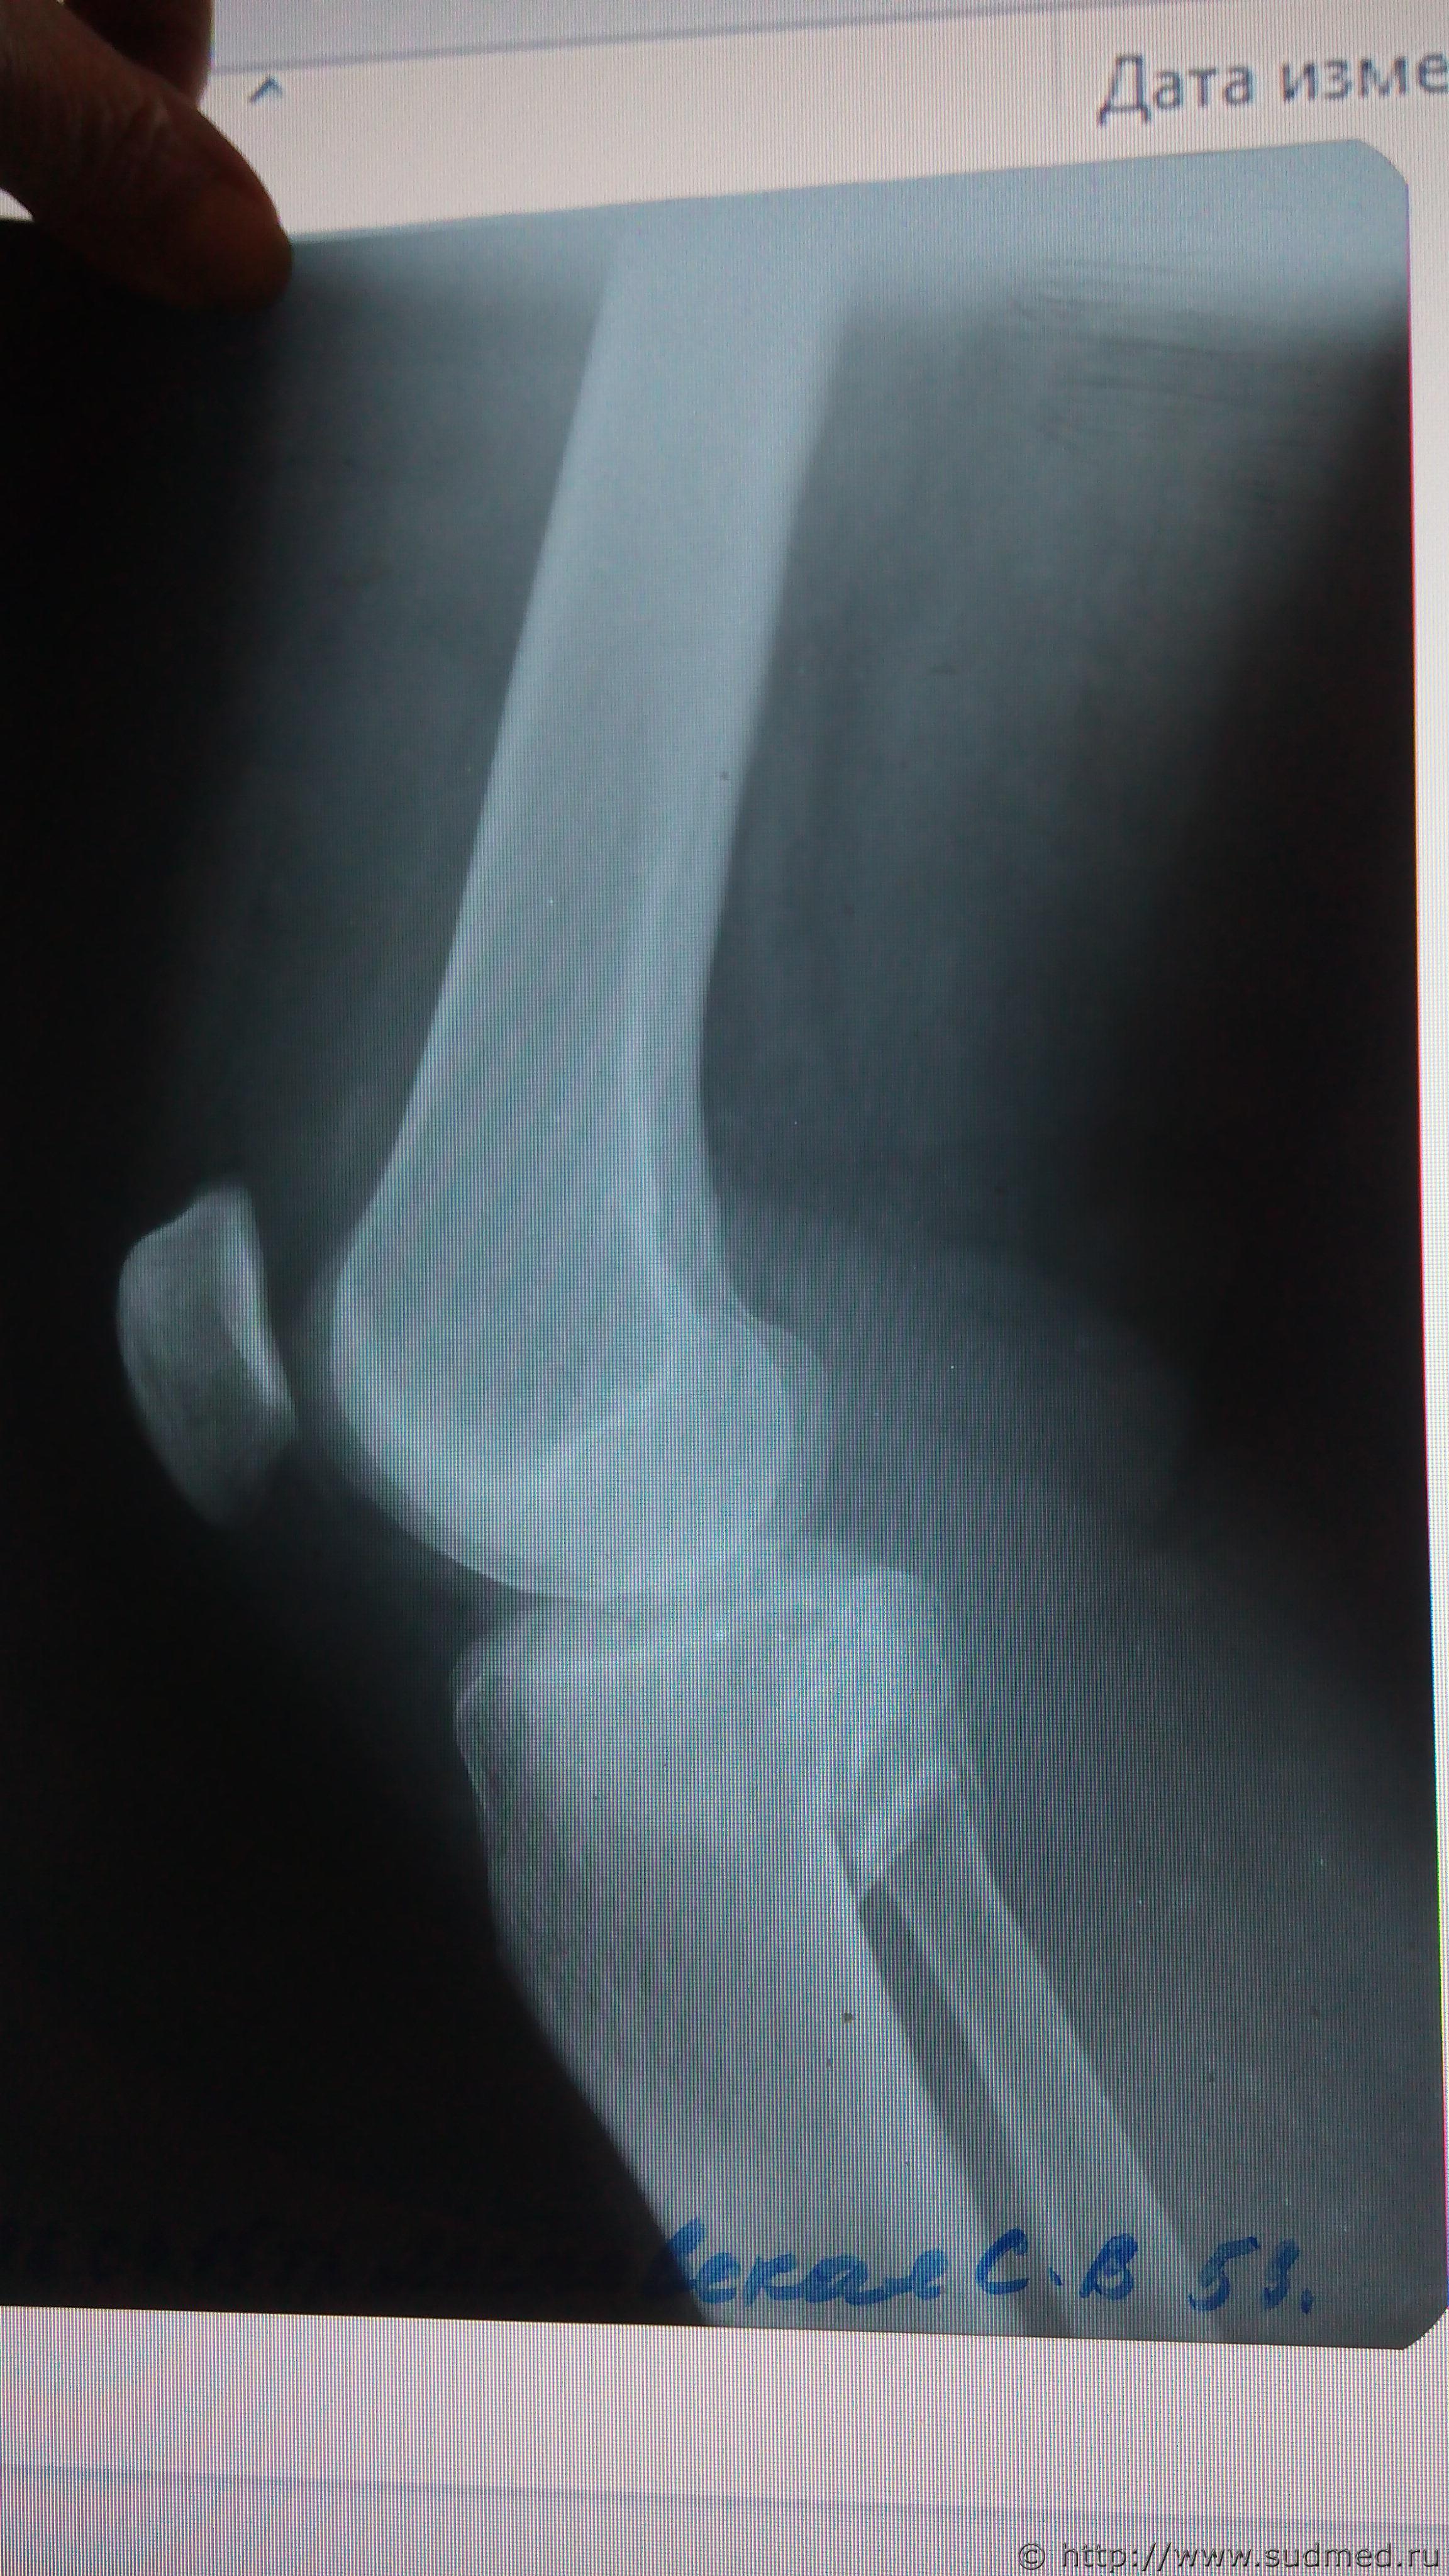

Первый рентген (до операции, 2 проекции) отсканировать есть возможность - давайте посмотрим.

Здравствуйте , постараюсь выложить снимки .

Эскизы прикрепленных изображений

Выложите все снимки. Это может быть важно: если перелом большеберцовой кости распространяется на её диафиз, то может быть тяжкий вред (п.6.11.8 приложения к Приказу Минздравсоцразвития от 24.04.08г. №194н). На единственном выложенном Вами снимке этого не видно, но зона перелома - совсем рядом с диафизом. Хотелось бы разобраться, как все обстоит на самом деле.

Спасибо за ответы , снимки послали должны появиться

Судебная медицина - Прикрепленное изображение Судебная медицина - Прикрепленное изображение Судебная медицина - Прикрепленное изображение